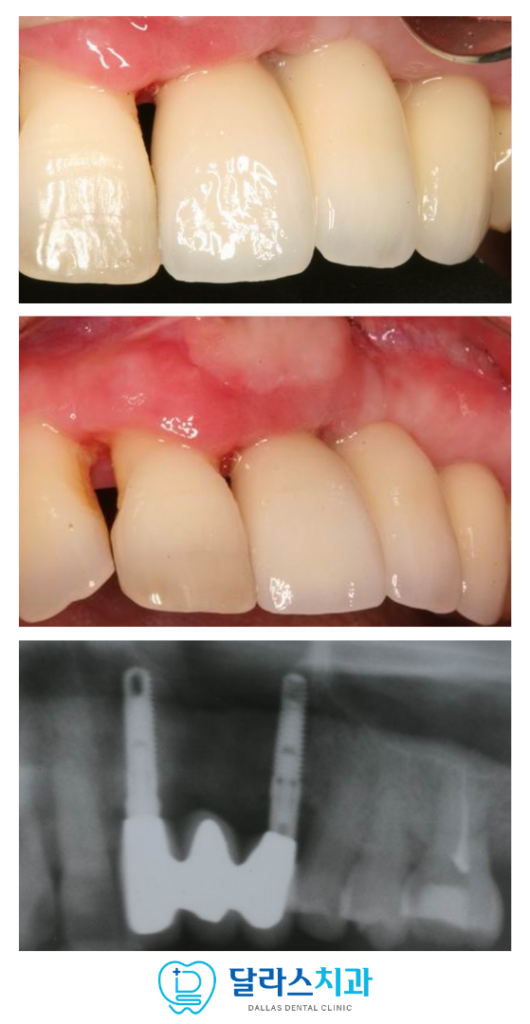

노원치과 달라스치과에서는 선천적인 구순구개열로 인해

구강 내 복합적인 불편함을 겪고 계셨던

여성 환자분의 임플란트 치료를 진행하였습니다.

해당 환자분은 과거에 여러 차례 수술을 받으면서

형성된 심한 흉터 조직 때문에 입술이 잘 벌어지지 않았으며

앞니부분의 치은 상태도 매우 악화된 상태였습니다.

가장 먼저, 상태가 좋지 못한 치아를 발치하였는데요.

이후 발치한 자리에 임플란트를 즉시 식립하면서 뼈이식을 진행하였고

노원치과 임플란트 식립 후 잇몸이 아문 뒤 흉터 조직을 개선하고

입술의 움직임을 원활하게 만들기 위해

근육 부착 위치를 조정하는 잇몸 성형 수술인 APF를 시행하였는데요.

이를 통해 입술이 당겨지는 힘을 줄여주고

칫솔이 들어갈 수 있는 공간을 확보하였습니다.

이와 더불어 임플란트 주변을 단단하게 지지해 줄 수 있도록

각화 치은 이식술(FGG)을 함께 진행하였습니다.

입천장 등에서 건강한 잇몸 조직을 채취하여

치아가 결손된 부위에 이식함으로써

외부 자극에 강한 잇몸 환경을 만들어 드렸습니다.

잇몸이 충분히 아물면서 제자리를 잡고 임플란트가 치조골과

골융합하는 시간을 충분하게 기다려준 뒤

임플란트 보철을 연결할 수 있도록 식립했던 임플란트의 연결 부위를

노출시켜주는 2차수술을 진행하였습니다.

처음과 이 때의 잇몸을 비교해보면

훨씬 충분하게 잇몸이 주변에 자리잡은 것을 볼 수 있는데요.

노원치과 환자분께서는 이전보다 입술을 움직이는 것이

한결 편안해지셨다고 말씀해주셨습니다.

흉터로 인해 좁았던 구강 내 공간이 개선되면서

스스로 구강 위생 관리를 꼼꼼하게 할 수 있는 토대가 마련되었고

새롭게 형성된 단단한 잇몸은 임플란트를 안정적으로 감싸주게 되었습니다.